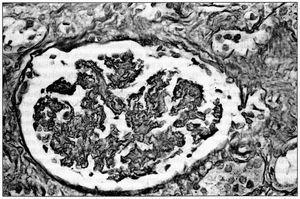

La biopsia renal (BR) demostró 18 glomérulos que presentaban afectación difusa de carácter isquémico con retracción y replegamiento de la pared capilar en las técnicas del PAS y argénticas, y rarefacción de la matriz mesangial. No se evidenció proliferación extracapilar. El intersticio presentaba fibroedema leve con infiltrado por células redondas, con atrofia tubular y cambios regenerativos del epitelio. Los vasos extraglomerulares de pequeño y mediano calibre presentaban cambios de arteriolopatía severa, necrosis fibrinoide de la pared y trombos fibrinoides intraluminales. La inmunofluorescencia fue negativa. Todo ello era compatible con HTA maligna (figura 2, figura 3 y figura 4).

Figura 4.